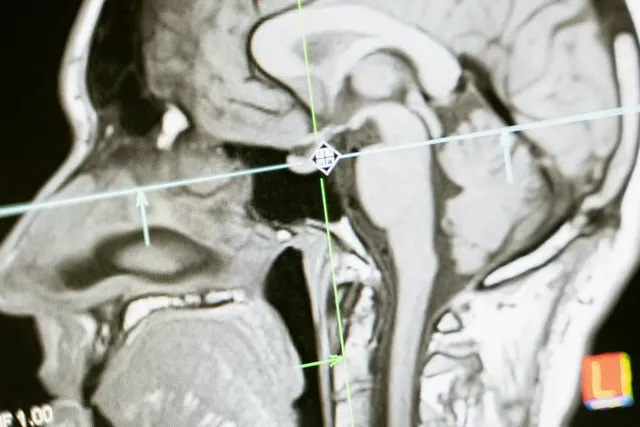

삼차신경은 얼굴부터 머리까지 담당하는 신경으로 물론 귀까지 포함되어 있습니다. 정확한 원인은 구조적으로 문제가 있을 수도 있고 다양합니다. 혈관에 의한 압박이나 혈관 문제 뇌동맥류, 신경계 질환 등 귀밑 통증이나 대부분 한쪽에서 통증이 발생하는 경우로 알려져 있습니다. 외상에 의한 경우도 있으니 증상을 잘 확인하시고 빠른 조치를 받아보셔야 합니다.